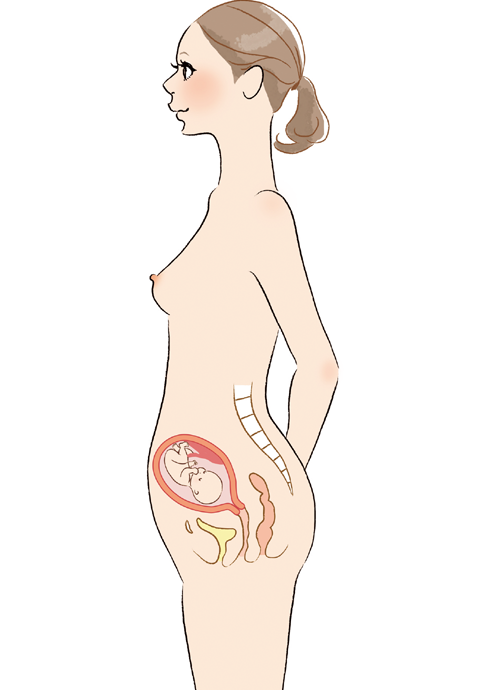

妊娠・出産による変化 その1 ~姿勢~東京都北区でお産ができる出産施設なら東京北医療センター産婦人科。

妊娠から出産までに母胎に起こる変化 妊娠中期ホームメイト。